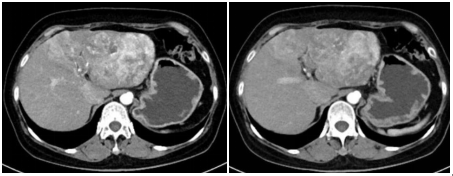

腹部增强CT(2020年9月):肝左叶巨大占位,考虑为肝细胞肝癌并门脉左支瘤栓可能。

图示:腹部增强CT(2020年9月)